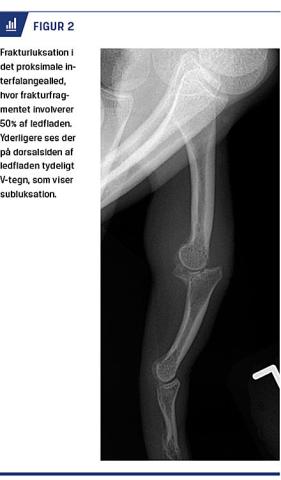

DROPFINGER

Formålet med behandlingen af dropfinger er at genoprette den aktive ekstension i DIP-leddet. Der er ikke konsensus om behandlingsmodalitet og -længde [26]. De fleste forfattere anbefaler dog operativ behandling ved åbne læsioner, involvering af mere end en tredjedel af ledfladen (Figur 3), subluksation, ledinkongruens og svigt af ikkeoperativ behandling [27]. Ved skinnebehandling holdes DIP-leddet kontinuerligt ekstenderet i en neutral stilling i seks uger, mens PIP-leddet er frit bevægeligt [27]. Behandlingen gentages, hvis DIP-leddet flekteres inden for seks uger, og der opstår reruptur eller refraktur [27]. Nogle forfattere anbefaler intermitterende immobilisering med efterfølgende brug af natskinne. 40% af de skinnebehandlede har imidlertid en persisterende strækkedefekt på 5-10 grader i DIP-leddet, mens 70% af patienterne har hudproblemer

Ikkedisplacerede, stabile frakturer og ossøs dropfinger med involvering af mindre end en tredjedel af ledfladen og uden subluksation kan behandles på en skadestuen. Intraartikulære frakturer, frakturluksationer i PIP-leddet, svært komminute og åbne frakturer (inkl. Seymour-fraktur), såvel som subkapitale frakturer og kondylfrakturer hos børn bør konfereres med eller henvises til håndkirurgisk vurdering. Tidlig mobilisering skal altid tilstræbes.